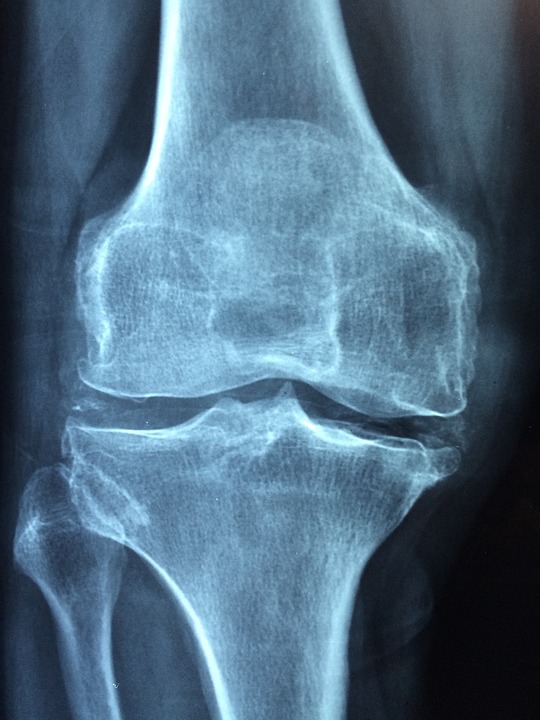

Die Diagnose von Rheuma kann komplex sein, da verschiedene Erkrankungen ähnliche Symptome verursachen können. In der Regel führt der Arzt zuerst eine gründliche körperliche Untersuchung durch und fragt nach den Symptomen und der Krankengeschichte des Patienten. Es können auch verschiedene Tests durchgeführt werden, wie z.B. Blutuntersuchungen, Röntgenbilder oder Magnetresonanztomographie (MRT), um das Ausmaß der Schäden oder Entzündungen zu beurteilen.